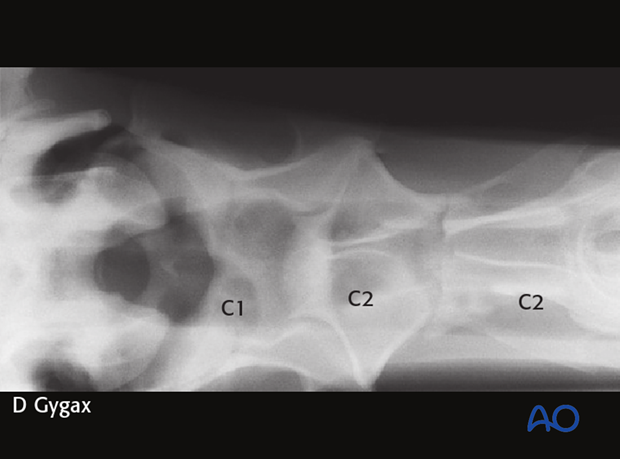

A 7-year-old Warmblood gelding was admitted with a 3-week history of neck stiffness. The horse had an acute onset of neck stiffness with no known trauma. According to the owner, the horse had initial mild signs of ataxia and weakness in the hind limbs.

Marked swelling was detectable in the proximal third of the neck at the level of the second cervical vertebra (C2).

The fracture was repaired using a 7-hole 4.5mm DCP. Optimal positioning of the plate and the length of the screws were facilitated by fluoroscopy.